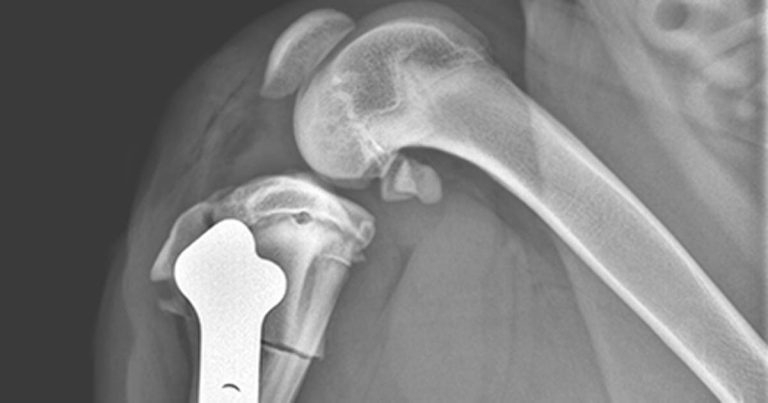

Figure 4. Mediolateral and caudocranial radiographic views of the left stifle – postoperative radiographs showed correct placement of the osteotomy and implants.

Routine suture removal was performed 12 days postoperatively and grade 2/5 lameness was documented following gait assessment. Mediolateral and caudocranial radiographic views of the left stifle were obtained six weeks postoperatively (Figure 4) using the same TPLO protocol as described previously. No residual lameness was reported by the owner, or noted on physical examination. The patient had full range of motion at the affected stifle joint. The radiographs revealed uniform fusion of the previous bone defect; implants were maintained in place.